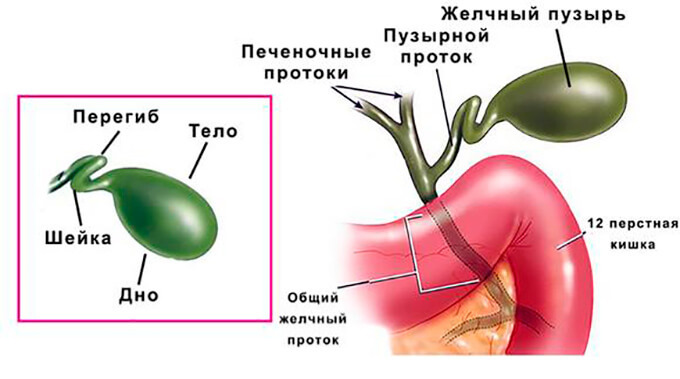

Анатомия и особенности Гартманова кармана желчного пузыря